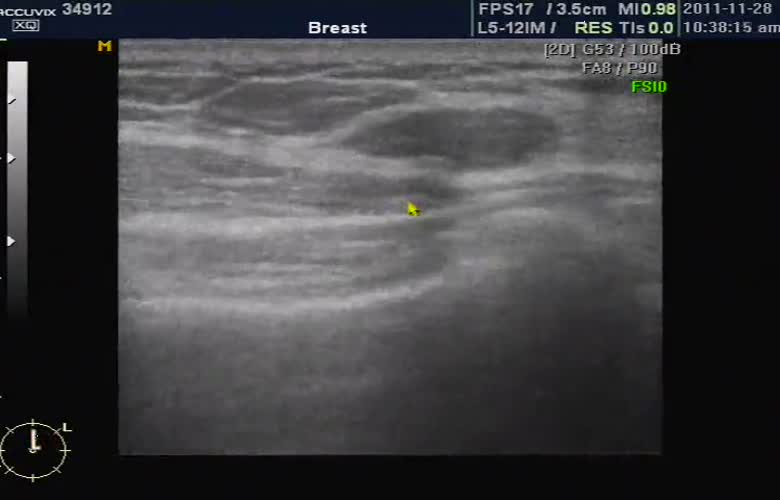

유방 초음파에서 본 결절의 모습입니다.

중심부에 검게 보이는 부분이 결절이며 이런 결절은 양성인 경우도 있고 악성인 경우도 있어서 크기나 모양 그리고 환자의 병력과 가족력 등을 감안하여 정밀 검사인 조직 검사 여부를 결정하게 됩니다.

왜냐하면 유방 초음파나 유방 X선 검사는 모두 결절이나 이상의 여부를 확인하는 것이지 최종적으로 악성인가 양성인가를 판다는 것은 아니기 때문입니다.